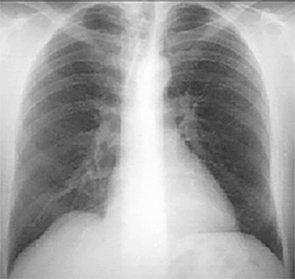

PA and Lateral

Click on the Xrays to enlarge them.

Choose the best interpretation of the chest X rays:

Normal with straight back syndrome

Normal

Dilated ascending aorta

Normal with bilateral accessory rib

Calcified coronary arteries